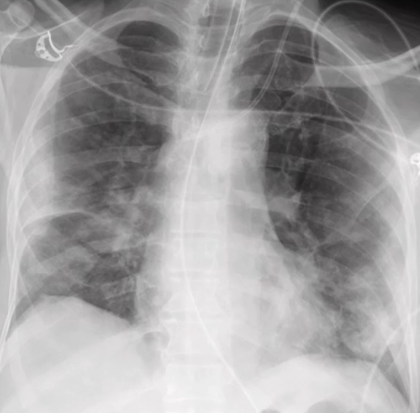

RA: atelectasis

a localized increase in density appearing as thin streaks or plates — “plate like atelectasis” to lobar collapse — displacement of lobar fissures

PT presents with difficulty breathing and a productive cough

What pathology is present?

atelectasis